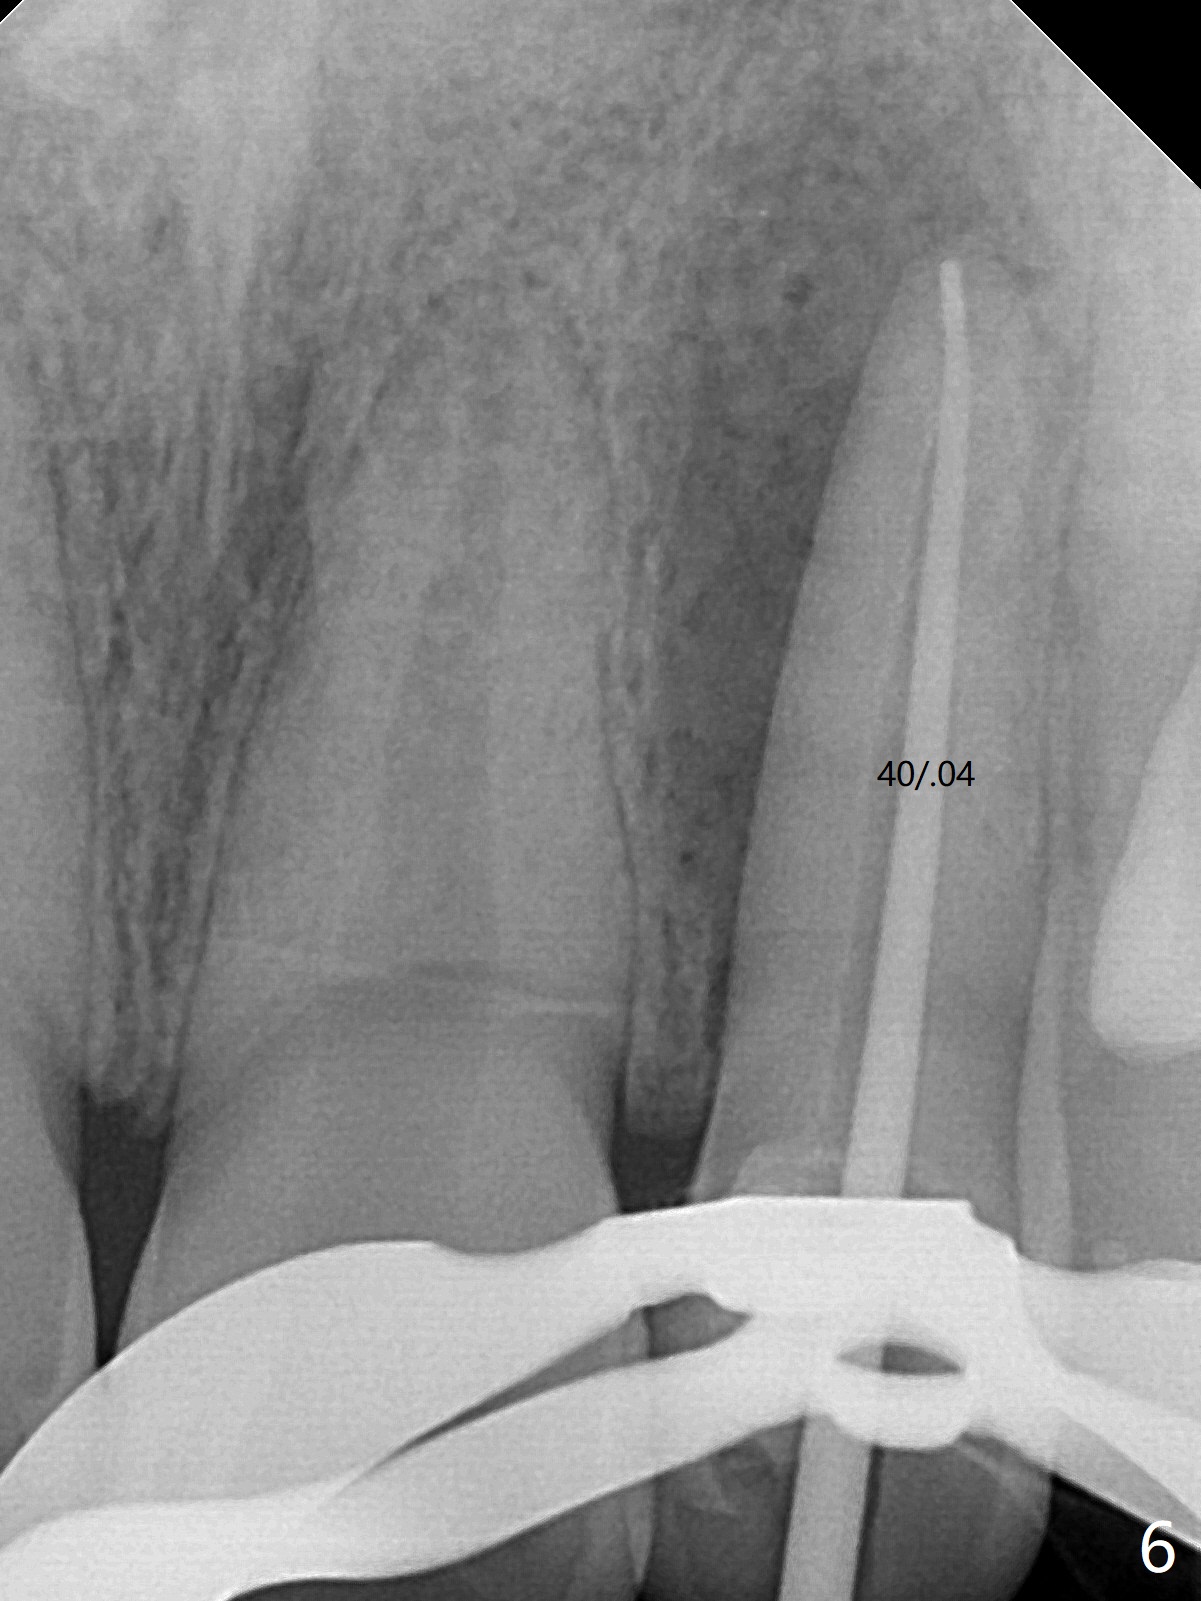

21岁女左上侧切牙根管治疗在别的诊所完成后出现瘘道(图一),近中阴影相当大(图二),应该如何处理?单独重做根管治疗足够吗?牙齿似乎没有松动,牙周袋正常,龋齿易感性高。牙列完整,仿佛没有咬合创伤迹象。可能由于经济问题,家长迟迟不带她去看专家。上个月我开始重做(图三:40/.04),能一次完成治疗吗?保险起见,放置氢氧化钙糊剂(图四)。一个月后病人回来,瘘道减小(图五),多次根管冲洗后,放置主牙胶尖(图六:40/.04),我当时在想根侧方阴影这么大,是不是有侧枝根管?如果扩根完善,根充时可能显示!是吗?其实这是最后根尖片(图七),40/.04主牙胶尖加三个fine, fine accessory gutta percha,并没有显示侧枝根管。